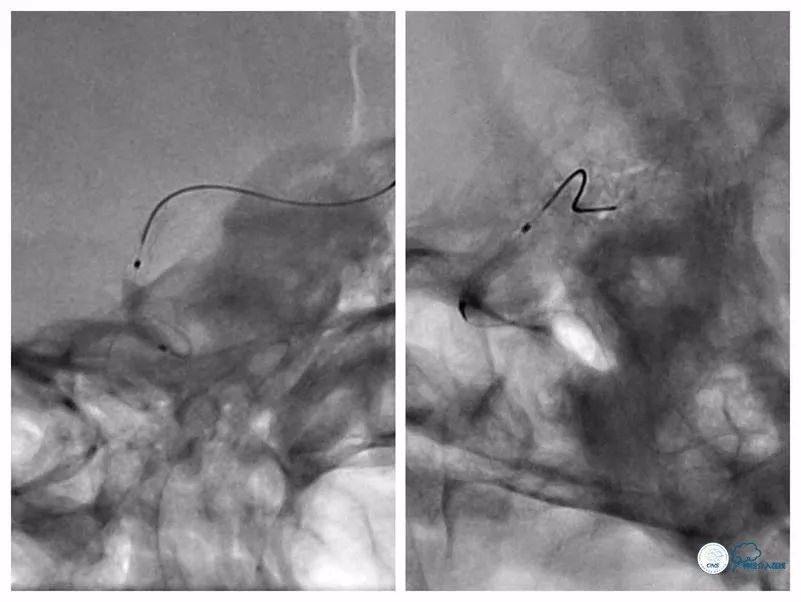

沿导丝送入两枚Apollo(2.5mm×8mm)球扩式支架由远及近释放(图11,12)。

图11

图12

其后造影显示支架贴壁可,前向血流TICI 3级(图13)。

图13